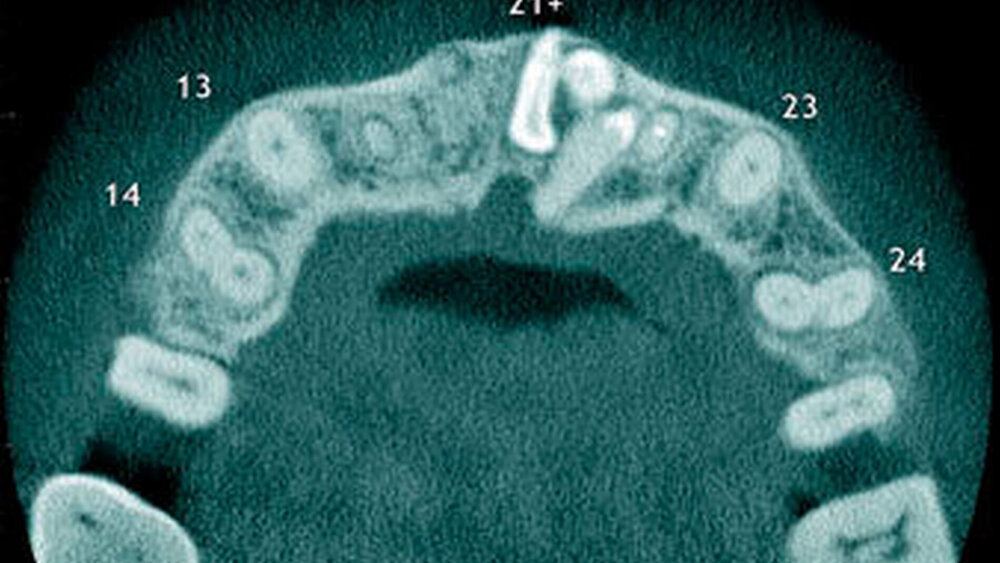

Überzählige Zähne können einzeln oder multipel auftreten [von Arx, 1990; Rajab Hamdan, 2002; Fernández Montenegro et al., 2006; Liu et al., 2007; Gündüz et al., 2008; Ferrés-Padró et al., 2009; Hyun et al., 2009]. Einzelne überzählige Zähne treten in 65,8 bis 80,5 Prozent, doppelte in 14,5 bis 27,7 Prozent und multiple in 0,6 bis 8 Prozent der Fälle auf [Rajab Hamdan, 2002; Fernández Montenegro et al., 2006; Liu et al., 2007; Ferrés-Padró et al., 2009; Hyun et al, 2009; Mossaz et al., 2014]. Einzelne oder doppelte überzählige Zähne finden sich typischerweise in der Oberkieferfront [Rajab Hamdan, 2002; Fernández Montenegroet al., 2006; Mossaz et al., 2014]. Multiple überzählige Zähne werden vor allem im Prämolarenbereich des Unterkiefers gefunden [Abbildung 4; YUSOF 1990, Ferrés-Padróet al., 2009; Wang Fan, 2011]. Multiple überzählige Zähne sind zudem oft mit anderen Erkrankungen oder Syndromen assoziiert, dazu gehören Lippen-Kiefer-Gaumenspalten, die cleidokraniale Dysplasie oder auch das Gardner-Syndrom. Bei Patienten mit einer Lippen-Kiefer-Gaumenspalte wird vermutet, dass sich die überzähligen Zähne aus der Fragmentierung der dentalen Lamina bei der Spaltbildung ergeben [Garvey et al., 1999; Wang Fan, 2011].

Überzählige Zähne werden nach ihrer Lage im Zahnbogen und auch aufgrund ihrer Morphologie eingeteilt. Basierend auf der Lage unterscheidet man bei überzähligen Zähnen zwischen Mesiodens (Oberkiefer median), zwischen den zentralen Inzisiven (Abbildungen 5 und 6), einem zusätzlichen Schneidezahn (zentral oder lateral), Eckzahn, Prämolar (Abbildung 7), Paramolar und Distomolar (Abbildungen 8). Mesiodentes werden am häufigsten dia- gnostiziert, wobei Prozentsätze zwischen 38,8 Prozent bis 86,3 Prozent der überzähligen Zähne in der Literatur zu finden sind [Salcido-García et al., 2004/38,8 Prozent, Fernández Montenegro et al., 2006 /46.9 Prozent; Mossaz et al., 2014/48.5 Prozent; Ferrés-Padró et al., 2009/53.2 Prozent; Schmuckli et al., 2010/75 Prozent; Rajab Hamdan 2002/83.2 Prozent; Liu et al., 2007/86.3 Prozent]. Überzählige Prämolaren und seitliche Schneidezähne sind die zweithäufigste Gruppe der überzähligen Zähne. Überzählige Eckzähne, Paramolaren und Distomolaren dagegen gelten als eher selten [Rajab Hamdan, 2002; Salcido- García et al., 2004; Liu et al., 2007; Ferrés-Padró et al., 2009; Schmuckli et al., 2010; Mossaz et al., 2014]. Einzig eine Spanische Gruppe [Fernández Montenegro et. al., 2006] berichtete, dass Paramolaren und Distomolaren insgesamt relativ häufig seien (18 Prozent, beziehungsweise 5,6 Prozent). Überzählige Zähne kommen im Ober- und Unterkiefer vor, wobei sich überzählige Schneidezähne in der Regel im Oberkiefer, überzählige Prämolaren sich dagegen eher im Unterkiefer befinden [Fernández Montenegro et al., 2006; Ferrés-Padró et al., 2009; Mossaz et al., 2014]. Überzählige Molaren wiederum treten normalerweise im Oberkiefer auf [Cassetta et al., 2014; Kaya et al., 2014].